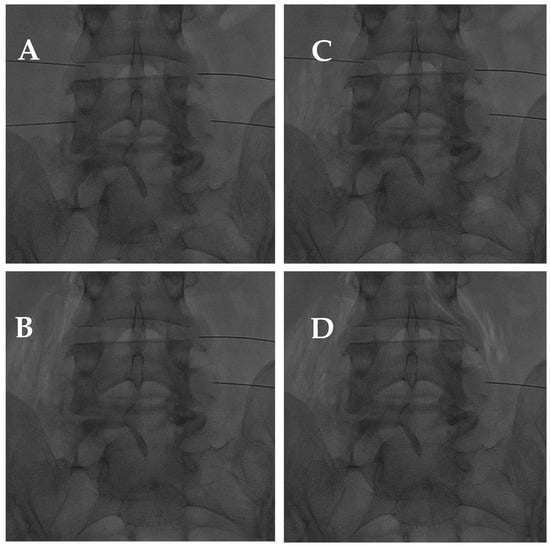

- Amoretti, N.; Amoretti, M.-E.; Hovorka, I.; Hauger, O.; Boileau, P.; Huwart, L. Percutaneous Facet Screw Fixation of Lumbar Spine with CT and Fluoroscopic Guidance: A Feasibility Study. Radiology 2013, 268, 548–555. [Google Scholar] [CrossRef]